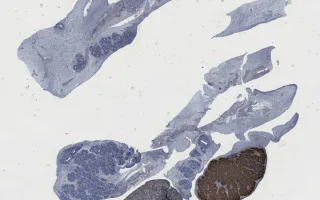

This fetus also had gonads with an indeterminate appearance on gross examination, corresponding histologically to gonads with both ovarian and testicular differentiation (“ovotestes”).

The overall findings in this fetus included increased growth parameters, congenital diaphragmatic hernia, nephroblastomatosis, and ovotestes.

This slide shows calretinin stain, highlighting sex-cord stromal elements. See Related Content section for other stains, specimen photograph and kidney slides: